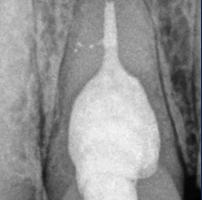

En la segunda sesión, 15 días después, realizamos la obturación convencional del tercio apical del canal con gutapercha, llenado de la cavidad reabsortiva con BIO-C ® REPAIR (Angelus, Londrina - Brasil) (Figura 7, 8 y 9), condensándolo contra las paredes con condensadores específicos y bolita de algodón humedecida y realizamos el sellado coronario con resina.

El BIO-C® REPAIR es un cemento reparador biocerámico listo para su uso. Se compone de silicato de calcio, aluminato de calcio, óxido de calcio, óxido de zirconio, óxido de hierro, dióxido

de silicio y agente de dispersión. El BIO-C® REPAIR presenta características superiores de adaptación marginal, biocompatibilidad, excelente radiopacidad y capacidad selladora en ambientes húmedos. Además de estas características, tiene como gran ventaja su facilidad de inserción a la cavidad reabsortiva

Figura 7 - BIO-C ® REPAIR (Angelus, Londrina - Brasil).

8 - Radiografia final

9 - Cavidad reabsortiva rellenada com BIO-C® REPAIR